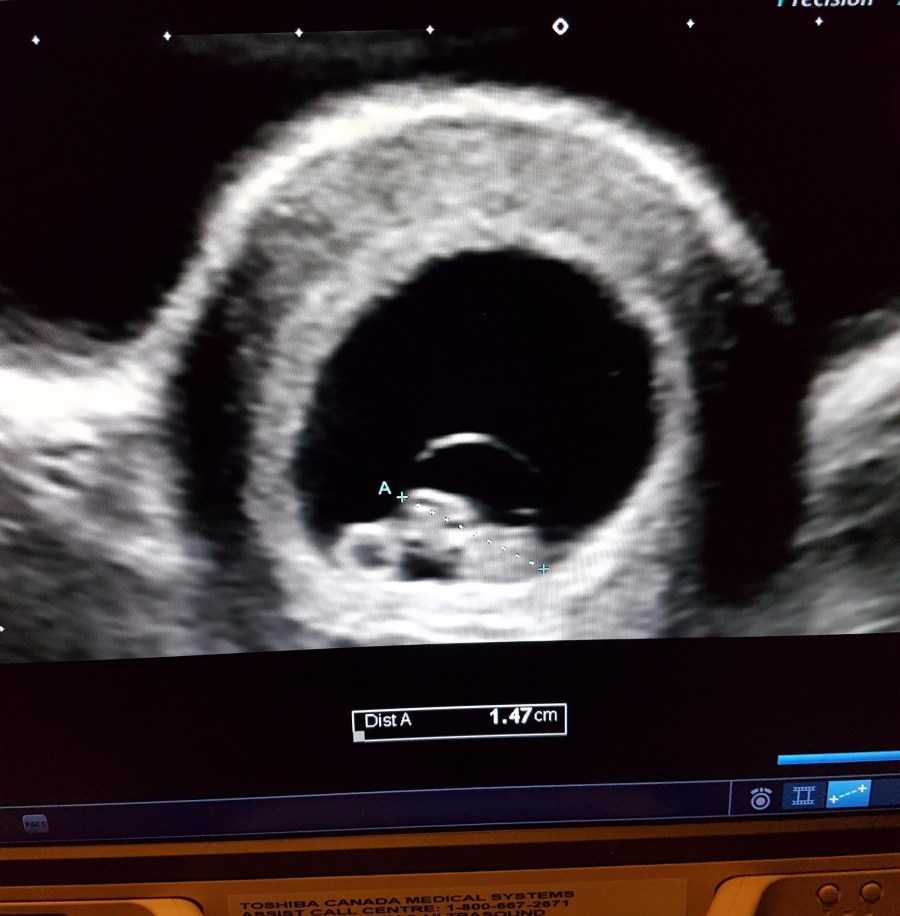

AND THEN THE BEST THING I’VE EVER SEEN SHOWED UP ON THE SCREEN!!! Our little baby, measuring 1 day ahead of my calculations at 7 weeks and 5 days!

Once they had taken all the measurements, they brought my husband in and let him snap a quick picture (above ^)! We even got to see the little heart flickering on the screen! I will never forget this moment, as it was honestly one of the best moments of my life!

The rest of that day was pretty much a blur for me. I sat there staring at the ultrasound pictures for hours, so happy that our little bean was doing well!